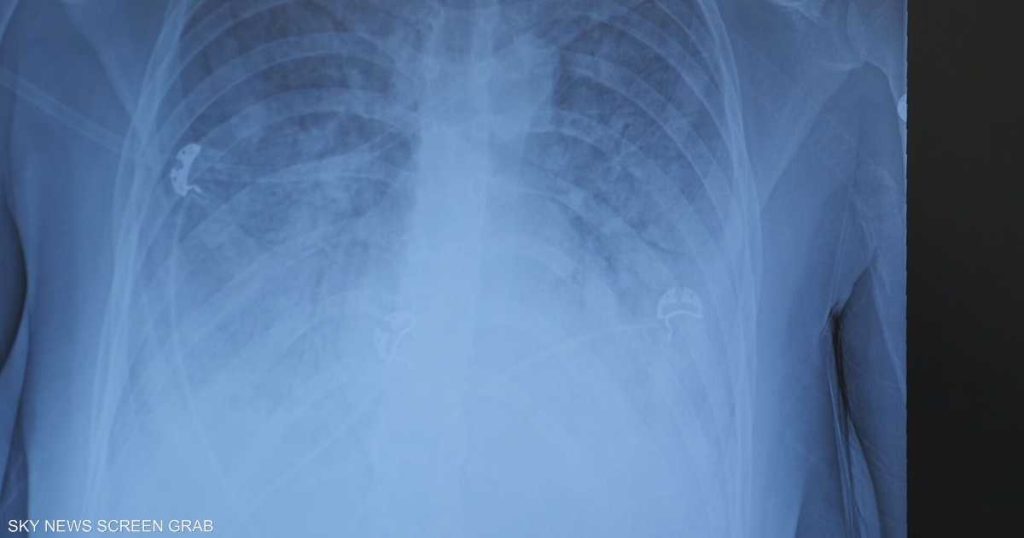

ونقل المراهق إلى المستشفى في حالة طارئة بعد تعرضه لفشل رئوي حاد، لتشخص حالته بإصابة خطيرة في الرئتين منعته من التنفس دون دعم خارجي.

وأشار إلى أن تدخين “الفيب” والسجائر الإلكترونية يسبب نفس الضرر تقريبا الذي تسببه السجائر التقليدية، بما في ذلك التهابات القصبات الهوائية نتيجة التعرض لمواد سامة، وهو ما ظهر في حالة الفتى الأردني الذي أصيب بفشل رئوي كامل.

وأضاف: “الآن نرى حالات حادة جدا، لم نكن نسمع بها بهذه السرعة مع السجائر التقليدية، مثل حالة المراهق الأردني الذي سيضطر للعيش على الأوكسجين مدى الحياة”.